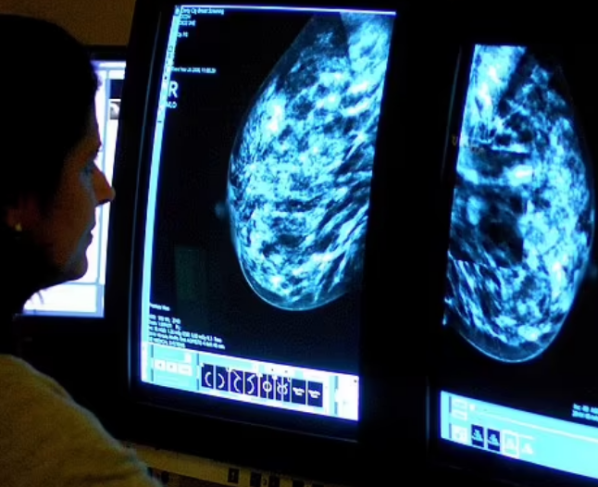

Um ensaio clínico internacional apontou avanços no tratamento do câncer de mama triplo negativo (TNBC), considerado um dos tipos mais agressivos da doença. A condição costuma atingir mulheres mais jovens, frequentemente apresenta resistência aos tratamentos tradicionais e representa entre 10% e 20% dos casos de câncer de mama.

Os resultados fazem parte do estudo TROPION-Breast02, que avaliou o uso do medicamento datopotamab deruxtecan (Dato-DXd), já aprovado para outros tipos de câncer de mama. Em pacientes com a forma avançada da doença, a nova terapia praticamente dobrou o tempo de sobrevida sem progressão do tumor — passando de 5,6 meses com quimioterapia padrão para 10,8 meses com o novo tratamento.

O estudo incluiu 644 pacientes com câncer localmente recorrente e inoperável ou metastático, que ainda não haviam recebido tratamento e não eram elegíveis à imunoterapia. Além do ganho no tempo sem progressão da doença, o medicamento reduziu os tumores em 63% dos casos, contra 29% entre os pacientes tratados com quimioterapia convencional. A sobrevida global mediana chegou a 23,7 meses.